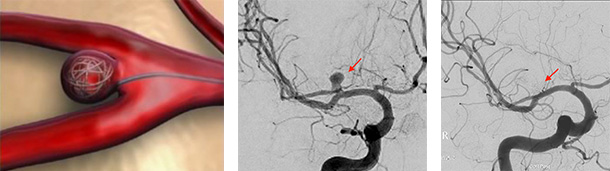

治療前

治療後

物が二重に見えるようになって発症した内頚動脈大型動脈瘤(矢印)の症例です。クリッピング術で直接動脈瘤をつぶすことができないため、バイパス術(矢印)を増設し内頚動脈を遮断することで動脈瘤を治療しました。